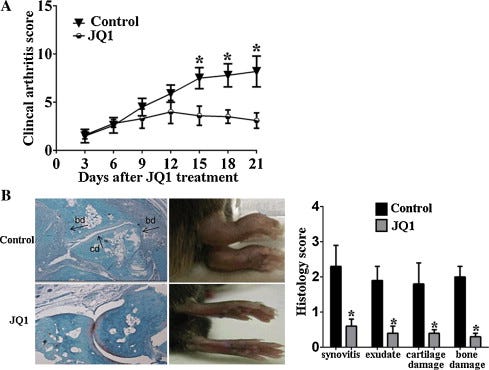

From 2015, Zhang et al used a mouse model to perform an in vivo investigation into the effects of BRD4 inhibition on TNFa-stimulated human rheumatoid arthritis fibroblast-like synoviocytes (RAF-FLS) behaviour21.

We aimed to explore the effects of bromodomain-containing protein 4 (BRD4) inhibition on tumor necrosis factor (TNF)-α-stimulated human rheumatoid arthritis fibroblast-like synoviocytes (RA-FLS) behavior and the therapeutic implications using BRD4 inhibitor JQ1 were explored in vivo. The levels of interleukin (IL)-1β, IL-6, IL-17 and IL-18 in cultural supernatants from TNFα-stimulated RA-FLS were measured by ELISA. RA-FLS migration and invasion in vitro were investigated using wound healing and Matrigel assay. Expression of signaling pathway proteins was measured by Western blot. The in vivo effects of BRD4 inhibitor JQ1 were elucidated using collagen-induced arthritis (CIA) mice. We found BRD4 silencing reduced the secretion of IL-1β, IL-6, IL-17 and IL-18 from TNFα-stimulated human RA-FLS. Downregulation of BRD4 inhibited FBS-induced migration and invasion of human RA-FLS. BRD4 silencing decreased the phosphorylation of c-Jun and activation of NFκB in TNFα-stimulated RA-FLS. In vivo, BRD4 inhibitor JQ1 reduced the inflammatory response, autoantibody production and joint damage of CIA model. Our data suggest for the first time that BRD4 inhibition has anti-inflammatory property in RA.

The CIA model was used to explore the therapeutic implications of the BRD4 inhibitor JQ1 in vivo. As expected, treatment with JQ1 significantly reduced the incidence rate of CIA (90% vs 20%, P < 0.01) and led to a significant attenuation in the clinical arthritis severity score (Fig. 5A). Furthermore, histological examination was conducted to illustrate the joint pathology in CIA mice. Consistent with the clinical arthritis score, the JQ1-treated mice showed a significant reduction in joint inflammation and damage (Fig. 5B).

IL-17 induces the production of several inflammatory mediators in the diseased synovium, which are further synergistically enhanced via combinations of IL-17 with other cytokines, including IL-1β, IL-6, IL-17 and IL-18, contributing to the hyperplasia and exacerbated inflammation observed in joints of RA patients [30]. Furthermore, these IL-17-driven events initiate several feedback-loop mechanisms leading to increased expansion of Th17 cells and thereby increased production of IL-17 [31]. In this study, we showed that BRD4 inhibition markedly downregulated the expression of IL-1β, IL-6, IL-17, IL-18 and TNFα in vitro and in CIA mice. Additionally, histological analysis indicated that JQ1 treatment reduced the synovial inflammation and destruction in CIA mice.

Taken together, we present evidence for the first time that the BRD4 inhibition can inhibit joint inflammation and FBS-induced migration and invasion of human RA-FLS via decreasing the phosphorylation of c-Jun and activation of NFκB. In vivo, JQ1 treatments reduced the inflammatory response, autoantibody production and joint damage of CIA model. Our data suggest that BRD4 may be a new target for human RA.